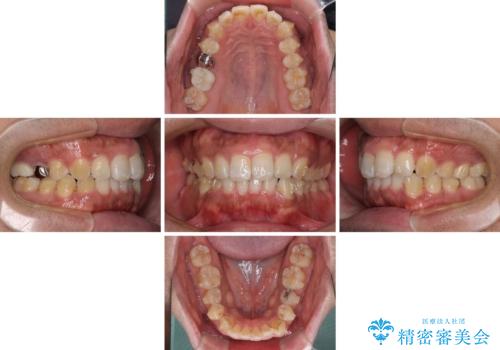

- 上下前歯部の叢生を気にして来院された患者様です。

レントゲン撮影により、右上奥歯が折れていることが分かりました。

患者様自身も何となく違和感を覚えていたとのことで、インプラント補綴治療を行うこととしました。

歯列不正は比較的軽微であったので、インビザラインによる矯正治療とし、矯正治療中にタイミングを見て抜歯とインプラント埋入を行う予定としました。